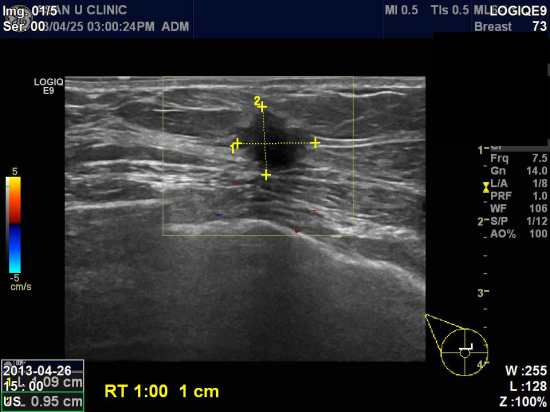

상기환자 건강검진시 유방촬영, 초음파 결절 소견으로 내원하신 64세 여성분이십니다.

본원 초음파상 우측 유방 1시방향에 1cm전후로 만져지는 딱딱한 혹 의심되어,

조직검사 시행하여 우측 유방암으로 진단되었습니다.